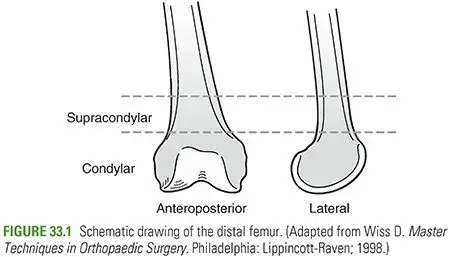

تُعد كسور عظم الفخذ السفلية (Distal Femoral Fractures) من الإصابات المعقدة التي تُصيب الجزء السفلي من عظم الفخذ، وتحديداً في منطقة تبعد حوالي 9 سنتيمترات عن خط مفصل الركبة. تُعرف هذه المنطقة باسم المنطقة فوق اللقمية أو داخل اللقمية، وهي حيوية لحركة الركبة واستقرارها. هذه الكسور ليست مجرد كسر بسيط في العظم؛ بل هي تحدٍ كبير لجراحي العظام والمرضى على حد سواء، نظراً لقربها من مفصل الركبة الحساس وأهمية هذا المفصل في الحركة اليومية.

يُستخدم نظام تصنيف AO/OTA بشكل أساسي لتصنيف كسور عظم الفخذ السفلية، وهو يُساعد الجراحين على فهم طبيعة الكسر وتحديد خطة العلاج المناسبة:

النوع A:

كسر خارج المفصل (فوق اللقمة).

النوع B:

كسر جزئي داخل المفصل (يُصيب لقمة واحدة).

النوع C:

كسر كامل داخل المفصل (يُصيب كلتا اللقمتين والجزء القريب من المفصل).

يُشير هذا التصنيف إلى مدى تعقيد الكسر والحاجة إلى دقة أكبر في الاستعادة التشريحية كلما زاد التورط المفصلي.

تشريح عظم الفخذ السفلي

يُشكل الجزء السفلي من عظم الفخذ منطقة معقدة تنتقل من جسم العظم الأسطواني في الأعلى إلى جزء عريض ومسطح في الأسفل، والذي يُشكل لقمتي الفخذ:

المنطقة فوق اللقمية:

هي المنطقة التي يتسع فيها العظم قبل اللقمتين، وتُصبح القشرة العظمية أرق هنا، مما يجعلها موقعاً شائعاً للكسور.

الوظيفة الحيوية لأنماط الكسور

الكسور فوق اللقمية (النوع A):

غالباً ما تكون مستعرضة أو مائلة. يتسبب شد عضلة الساق في ميلان الجزء البعيد للخلف.

الكسور بين اللقمتين (النوع C):

تُصيب السطح المفصلي، وغالباً ما تكون على شكل حرف T أو Y. تُساهم قوى القص والارتطام والصدمة المباشرة في تفتت الكسر.

كسور اللقمة (النوع B):

تُؤدي الأحمال المحورية المباشرة أو أحمال التقوس/التحدب إلى كسور لقمة واحدة.